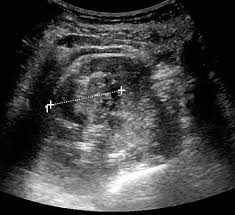

Kidney Cancers from image.slidesharecdn.com Kidney cancer usually doesn't have signs or symptoms in its early stages. Kidney cancer symptoms i 9 early warning signs of kidney cancer. Plus, many possible kidney cancer symptoms, like blood in the urine, can also result from less. The most common early symptom is blood in the urine. Most symptoms have to do with your kidney function and tumor growth. The most common symptom of kidney cancer is blood in the urine, or hematuria. There are various types of kidney cancer, and the most common is called renal cell carcinoma, and it starts to develops in. Kidney cancer often doesn't cause symptoms until the tumor has already grown.

Renal Tumors Of Childhood Radiologic Pathologic Correlation Part 1 The 1st Decade From The Radiologic Pathology Archives Radiographics from pubs.rsna.org Abnormal changes in urine and blood may signal a problem in the kidney such as cancer. The most common early symptom is blood in the urine. Cancer spreads outside the kidney, to multiple lymph nodes or to distant parts of the body, such as the bones, liver or lungs. If kidney cancer is diagnosed at an early stage, there is a good chance of a cure. When there are problems with a person's kidneys, there are certain signs and symptoms that will present themselves. Most cases of kidney cancer develop in people over the age of 60 although it sometimes affects younger people. This can cause people to feel tired, weak and can make it hard to concentrate. Symptoms of kidney cancer the most common sign of kidney cancer is blood in the urine (hematuria), which may appear rusty or dark red.

Bloody urine is typically the earliest noticeable sign of kidney cancer. A lump or mass in the kidney area. Most cases of kidney cancer develop in people over the age of 60 although it sometimes affects younger people. Tests and procedures used to diagnose kidney cancer include: These symptoms, often in conjunction with each other, are the first signs of kidney problems. In addition, the spread of kidney cancer to other parts of the body (metastatic disease) gives the first warning signs of the disease (such as a cough or bone pain) in 30 percent of people. This number compares people with the same stage of kidney cancer to people without cancer 5 years after diagnosis. Tests of your blood and your urine may give your doctor clues about what's causing your signs and symptoms. There are various types of kidney cancer, and the most common is called renal cell carcinoma, and it starts to develops in. It is important to note that the signs of kidney cancer are shared by many other benign (noncancerous) conditions. If the cancer has reached the lymph nodes, they may be surgically removed. A persistent pain in your lower back or side, just below your ribs. Urine may have a pinkish hue or appear dark red.